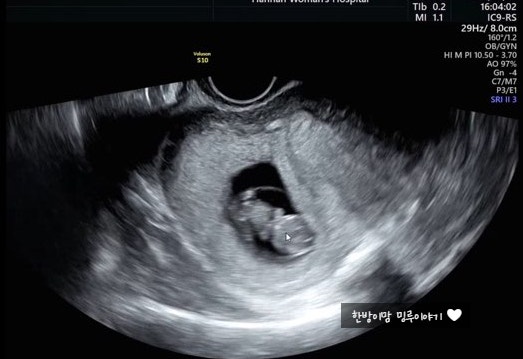

임산부일기_1. 9주차 초음파. 안녕✋ 꼬물꼬물 하리보야 (전주 한나산부인과)

오늘은, 9주차때 갔다온 전주한나산부인과 기록!! 묵혀둔..? 의도하지 않은 묵혀둔 한방이의 초음파! 세상...